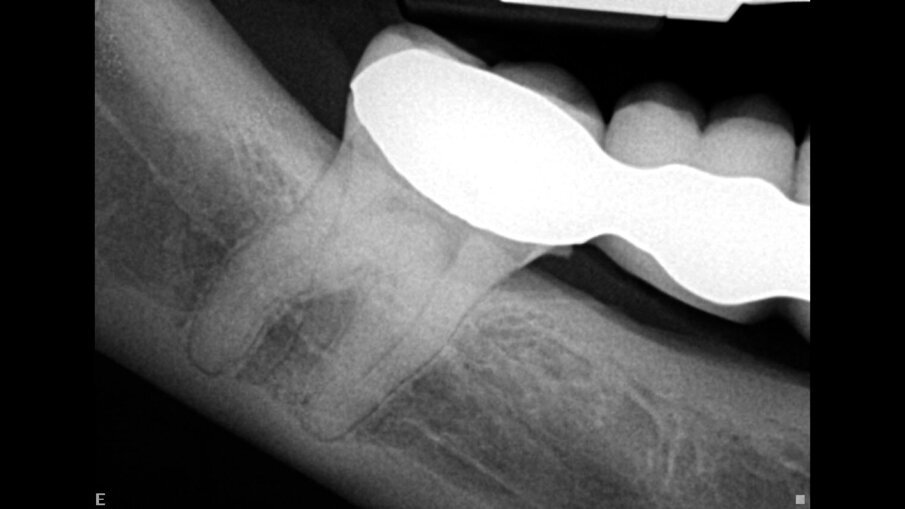

Ovaj pacijent je hitno došao zbog oštrog bola u drugom maksilarnom molaru. Ovo je potvrđeno kliničkim pregledom. Napravljen je standardni radiograf (Sl. 1), koji pokazuje veoma složenu anatomiju i kalcifikovanu pulpnu komoru. Istorija ovog zuba, kako je opisao pacijent, bila je da je na njega postavljen inlej i nakon nekog vremena se pojavila nelagodnost koja je trajala nekoliko godina bez lečenja. Na pregledu mu je rečeno da je sve u redu.

Sl. 1: Rendgen snimak pre operacije, koji pokazuje veoma složen sistem korenskih kanala i kalcifikovanu pulpnu komoru